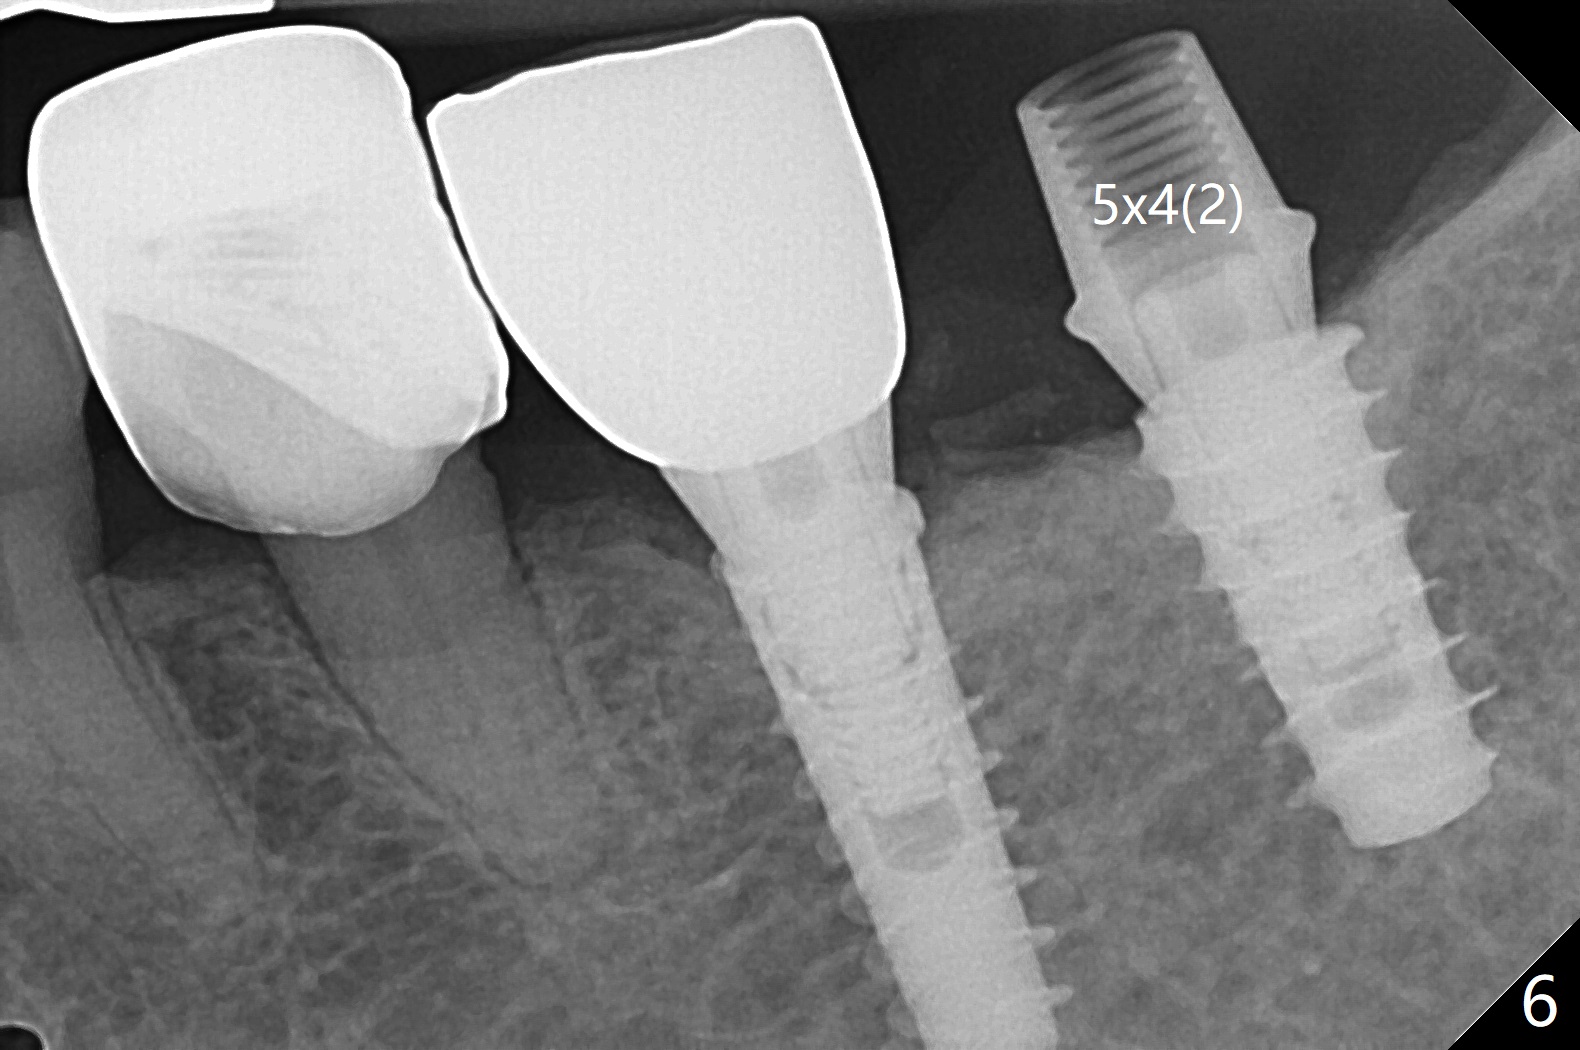

Because of the narrow ridge top at the sites of #19 and 18, it is reduced (Fig.1 arrowheads) prior to initial osteotomy with 1.6 mm pilot drill.  After Magic Drills (3.3 and 4.3 mm at #19 and 18, respectively), 4x11 and 5x9 mm IBS implants are placed with insertion torque >35 Ncm with immediate placement of pair abutments (4.5x5.7(2) and 6.5x4(2) mm, Fig.2).  In fact these sites are converted to a premolar and a 1st molar (because narrow ridge at #19).  Following GBR and suturing, periodontal dressing is applied around the abutments for increased retention.  The regional ridge reduction makes Marking Bur unnecessary (because of flat ridge top and the soft bone in this case) and more importantly there is no thread exposure upon implant placement.  The trimmed site (concavity) is favorable for bone graft and membrane placement.  One month postop, loose perio dressing is removed and replaced by a splinted nonfunctional provisional.  The implant sites look normal nearly 3 months postop; there is no bone loss (Fig.3).  Impression is taken.  The crown/abutment at #18 is loose 3 years 2 months post cementation; when the crown/abutment is retightened, the abutment remains incompletely seated (Fig.4 <) in spite of reduction of the proximal contact (arrow).  It may be due to the block of the distal crest (*).  After use of 5.5 mm profile drill, the 6.5x4(2) mm abutment remains unseated (Fig.5).  The smaller one (5x4(2) mm, Fig.6) is seated.  When the redo crown is cemented, the surrounding gingiva is healthy with a short papilla between the implant crowns (Fig.7).